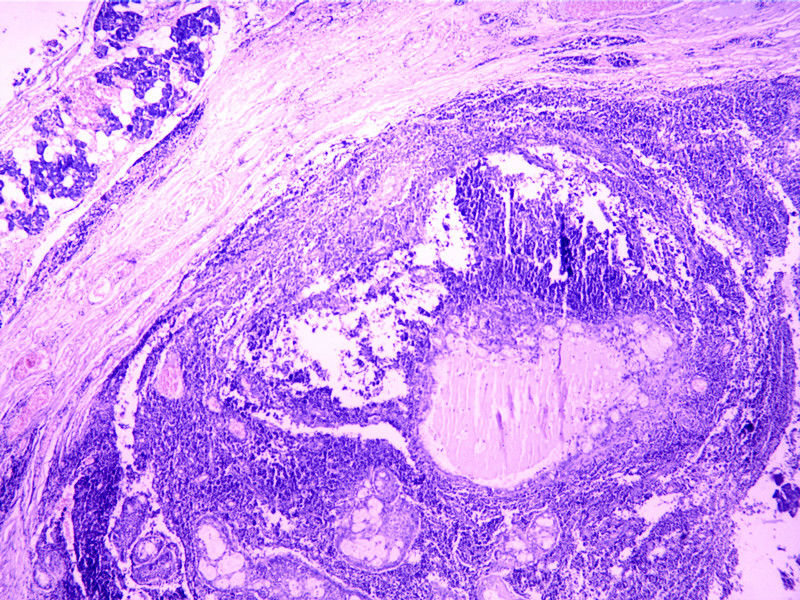

这个肿物有些Hold不住

性别

女

年龄

46

临床诊断

肿物

临床症状

发现肿物3年

标本名称

腮腺

大体所见

肿物V3*2.5*2.5cm,界清。

考虑转移癌。